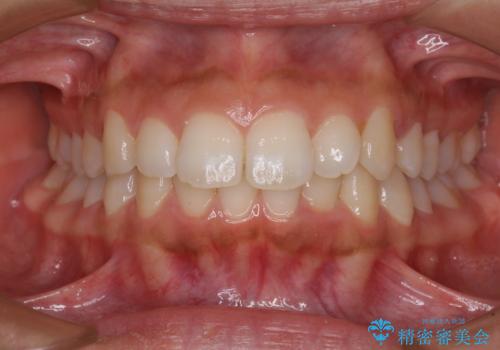

- 出っ歯で唇が閉じにくいとのことで来院された患者様です。

顎先に力を入れないと唇が閉じきれない口元であったので、上下左右の第一小臼歯4本を抜歯して、ワイヤー装置にて矯正治療を行うこととしました。

2年から2年半の治療期間を想定しており、予定通りの期間で無事に終了することができました。

唇や顎先に力を入れないなくてもスムーズに唇を閉じることができるようになりました。